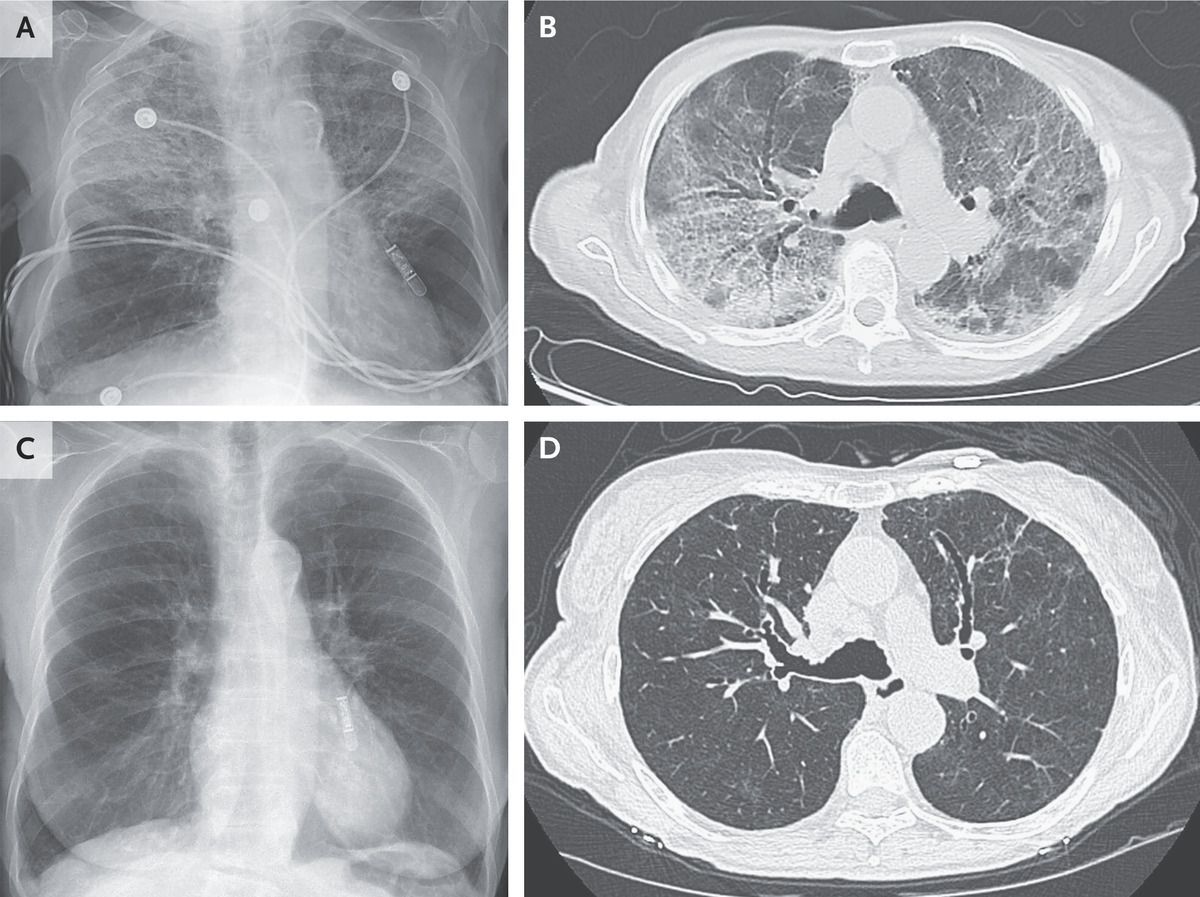

A 95-year-old woman presented to the emergency department with a 4-week history of dyspnea and dry cough. She had not previously reported these symptoms to her doctor. She reported no fevers. For the past 6 months, she had been taking nitrofurantoin daily to prevent recurrent urinary tract infections. Her oxygen saturation was 83% while she was breathing ambient air. On physical examination, inspiratory crackles were noted in the upper lung fields. There was no jugular venous distention or edema. Laboratory studies showed neutrophilic leukocytosis but no eosinophilia or elevations in aminotransferase levels. A chest radiograph was notable for patchy alveolar opacities that were most prominent in the upper lobes (Panel A). A sputum culture and viral respiratory panel were negative. A subsequent computed tomographic image of the chest showed ground-glass and reticular opacities with upper-lobe predominance and moderate bronchiectasis (Panel B). Owing to the patient’s imaging findings and long-term nitrofurantoin exposure, a diagnosis of chronic nitrofurantoin-induced lung injury was made. In patients with nitrofurantoin-induced lung injury, the radiologic findings are varied and may be diffusely distributed or localized. Treatment with nitrofurantoin was stopped, and a prednisone taper was prescribed. One week later, the patient’s symptoms had abated. Two months later, repeat imaging showed that the opacities had nearly resolved and the bronchiectasis had stabilized (Panels C and D, respectively).